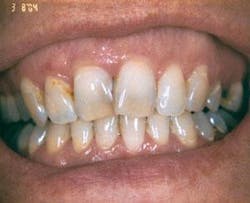

On her first visit in March 2004, a comprehensive exam, full-mouth radiographs, oral cancer screening, periodontal assessment, TMJ assessment, and intraoral photographs were taken. During her patient interview, April agreed that her dental health was “pretty poor.” She was concerned about two root canal treatments recently performed overseas. She was also worried about the obvious cavities and deteriorating amalgam restorations that were present. Cold sensitivity and chronic food impaction were present throughout her mouth. Her biggest wish was to have a whiter and straighter smile (Figure 1).